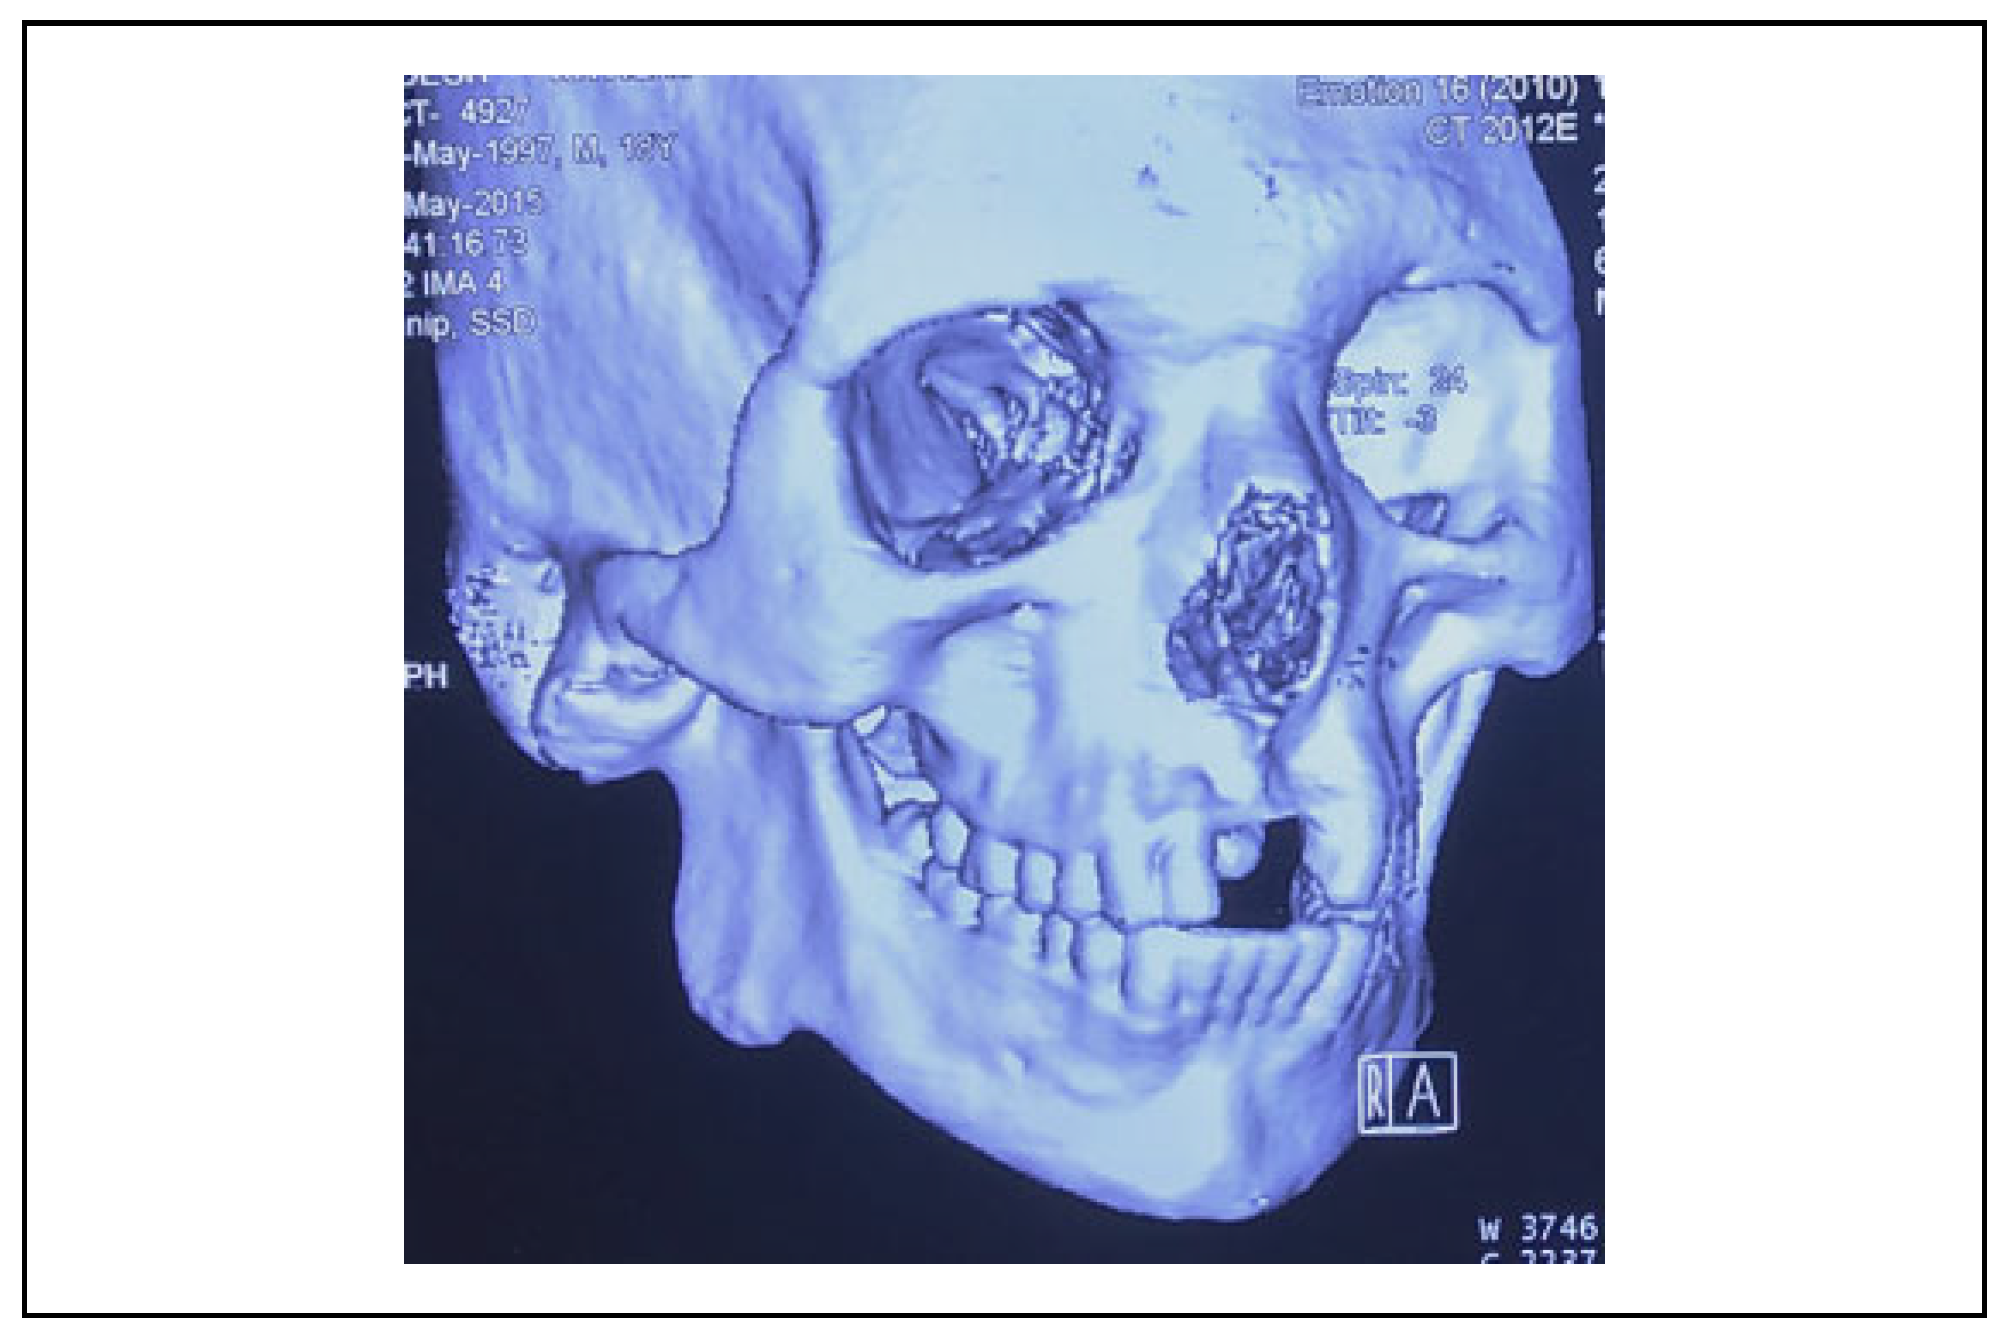

A Clinical and Radiological Investigation of the Use of Dermal Fat Graft as an Interpositional Material in Temporomandibular Joint Ankylosis Surgery

Rahman, S.A.; Rahman, T.; Hashmi, G.S.; Ahmed, S.S.; Ansari, M.K.; Sami, A. A Clinical and Radiological Investigation of the Use of Dermal Fat Graft as an Interpositional Material in Temporomandibular Joint Ankylosis Surgery. Craniomaxillofac. Trauma Reconstr. 2020, 13, 53-58. https://doi.org/10.1177/1943387520903876